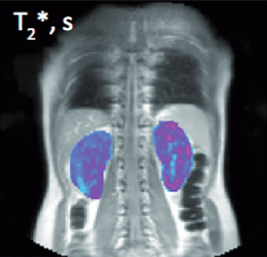

From study design to final reporting, Bioxydyn delivers repeatable MRI biomarkers that reveal tissue function, physiology and change. Our operational excellence and metrology help you compare results across sites, scanners and timepoints.

We're Bioxydyn - delivering quantitative MR biomarkers for pharmaceutical, biotech and academic studies. We combine scientifically leading methods with robust multi-centre study management and transparent analysis, turning complex images into repeatable measurements that support confident decisions.

Disease areas and services supporting quantitative MRI biomarkers across clinical trials.